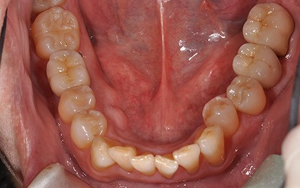

![]()

下の歯(左下奥から2番目から、セラミックインレー、メタルボンドインプラント、セラミックインレー、

右下は奥からメタルボンドクラウン、メタルボンドインプラント、セラミックインレー)